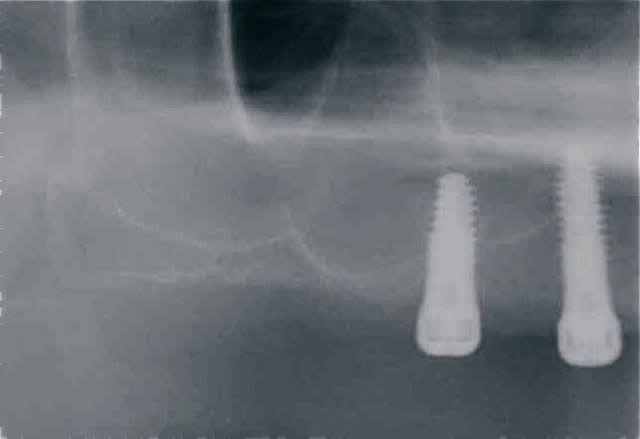

Cas clinique n° 2

dans un post précédent je t'ai demandé des radios et la superposition de la planification et des radios post op montrait un delta de 15 à 20° de implants

Pour calculer la précision post- opératoire il faut la comparer à une position déterminée pré-opératoirement, peut tu nous montrer la planification du cas que tu montre et au moins une OTP.

Quelle méthode utilises-tu pour calculer l’imprécision du système présenté ?